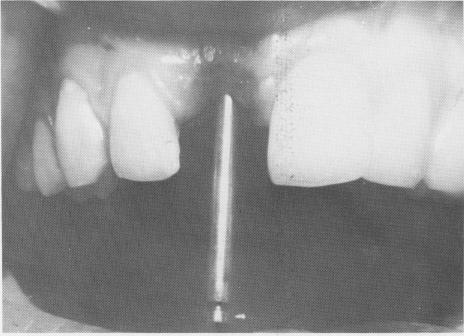

The operation for placing the implant began with a spear-point entering bur (Fig. 8-26), continued with the various size helical burs, and finished with the insertion of the implant (Fig. 8-27). The restoration was cemented into position (Fig. 8-28) and x-rayed (Fig. 8-29).

Fig. 8-26. A spear-point entering bur is used, followed by the various sized helical burs.

Fig. 8-27. The vent-plant is then threaded into position.